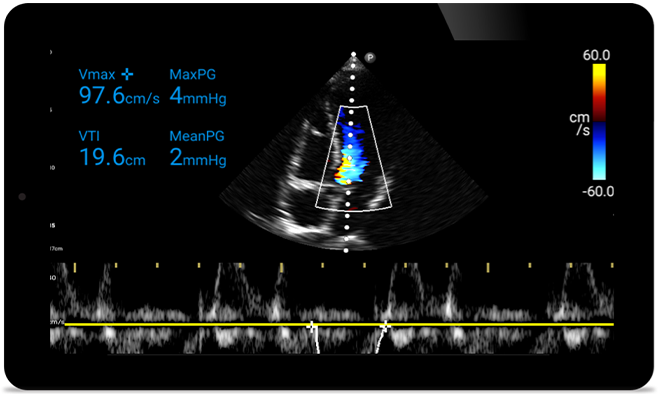

Reageer sneller om hun hart te beschermen

Wanneer elke seconde telt, kan draagbare echografie het verschil maken. Lumify kan de HD-beelden leveren, waar en wanneer u die nodig heeft.

Mogelijkheid om cardiomyopathie ongedaan te maken